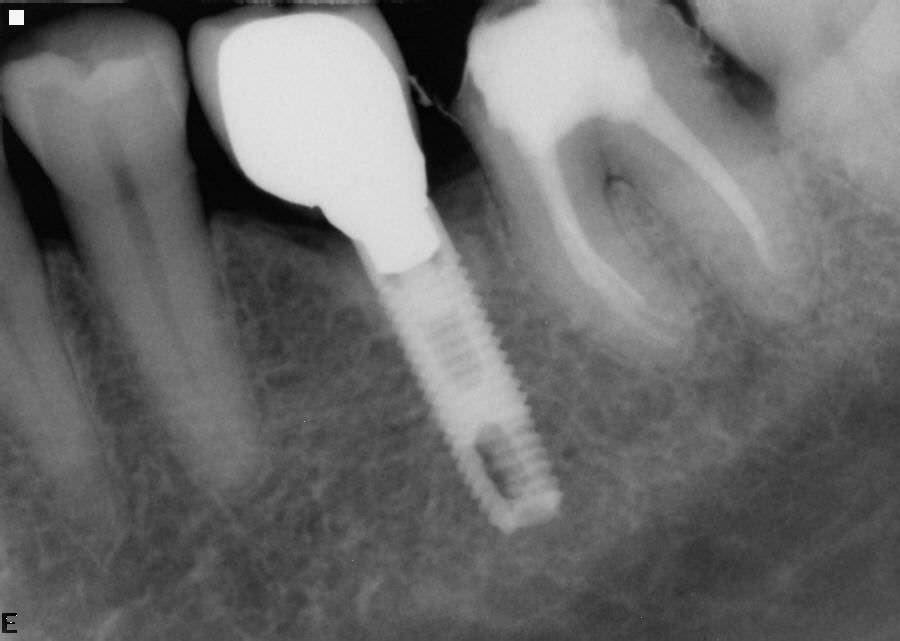

אחד הסיבוכים המאכזבים ביותר שעלולים להתרחש במהלך הכנה כימו-מכאנית של תעלת השורש הוא שבר של מכשיר אנדודונטי בתוך התעלה.

הטיפול בשן עם מכשיר מופרד בתעלת השורש תלוי בפרוגנוזה הצפויה של השן. במידה והיתרונות מפינוי המכשיר עולים על פני הסיכון לפגוע בשלמות השורש במהלך פינויו, נעשה ניסיון לעקוף או לפנות את המכשיר במהלך טיפול שורש. לדוגמה, ייעשה מאמץ לפנות מכשיר שנשבר בתחילת ההכנה של תעלת השורש המזוהמת הממוקם בשליש כותרתי של התעלה. העדיפות תינתן תמיד לעקיפת המכשיר ולא לפינויו בשל החשש כי פעולה זו עלולה להחליש את השורש ואף לגרום לניקובו במהלך הניסיונות לפינוי המכשיר .